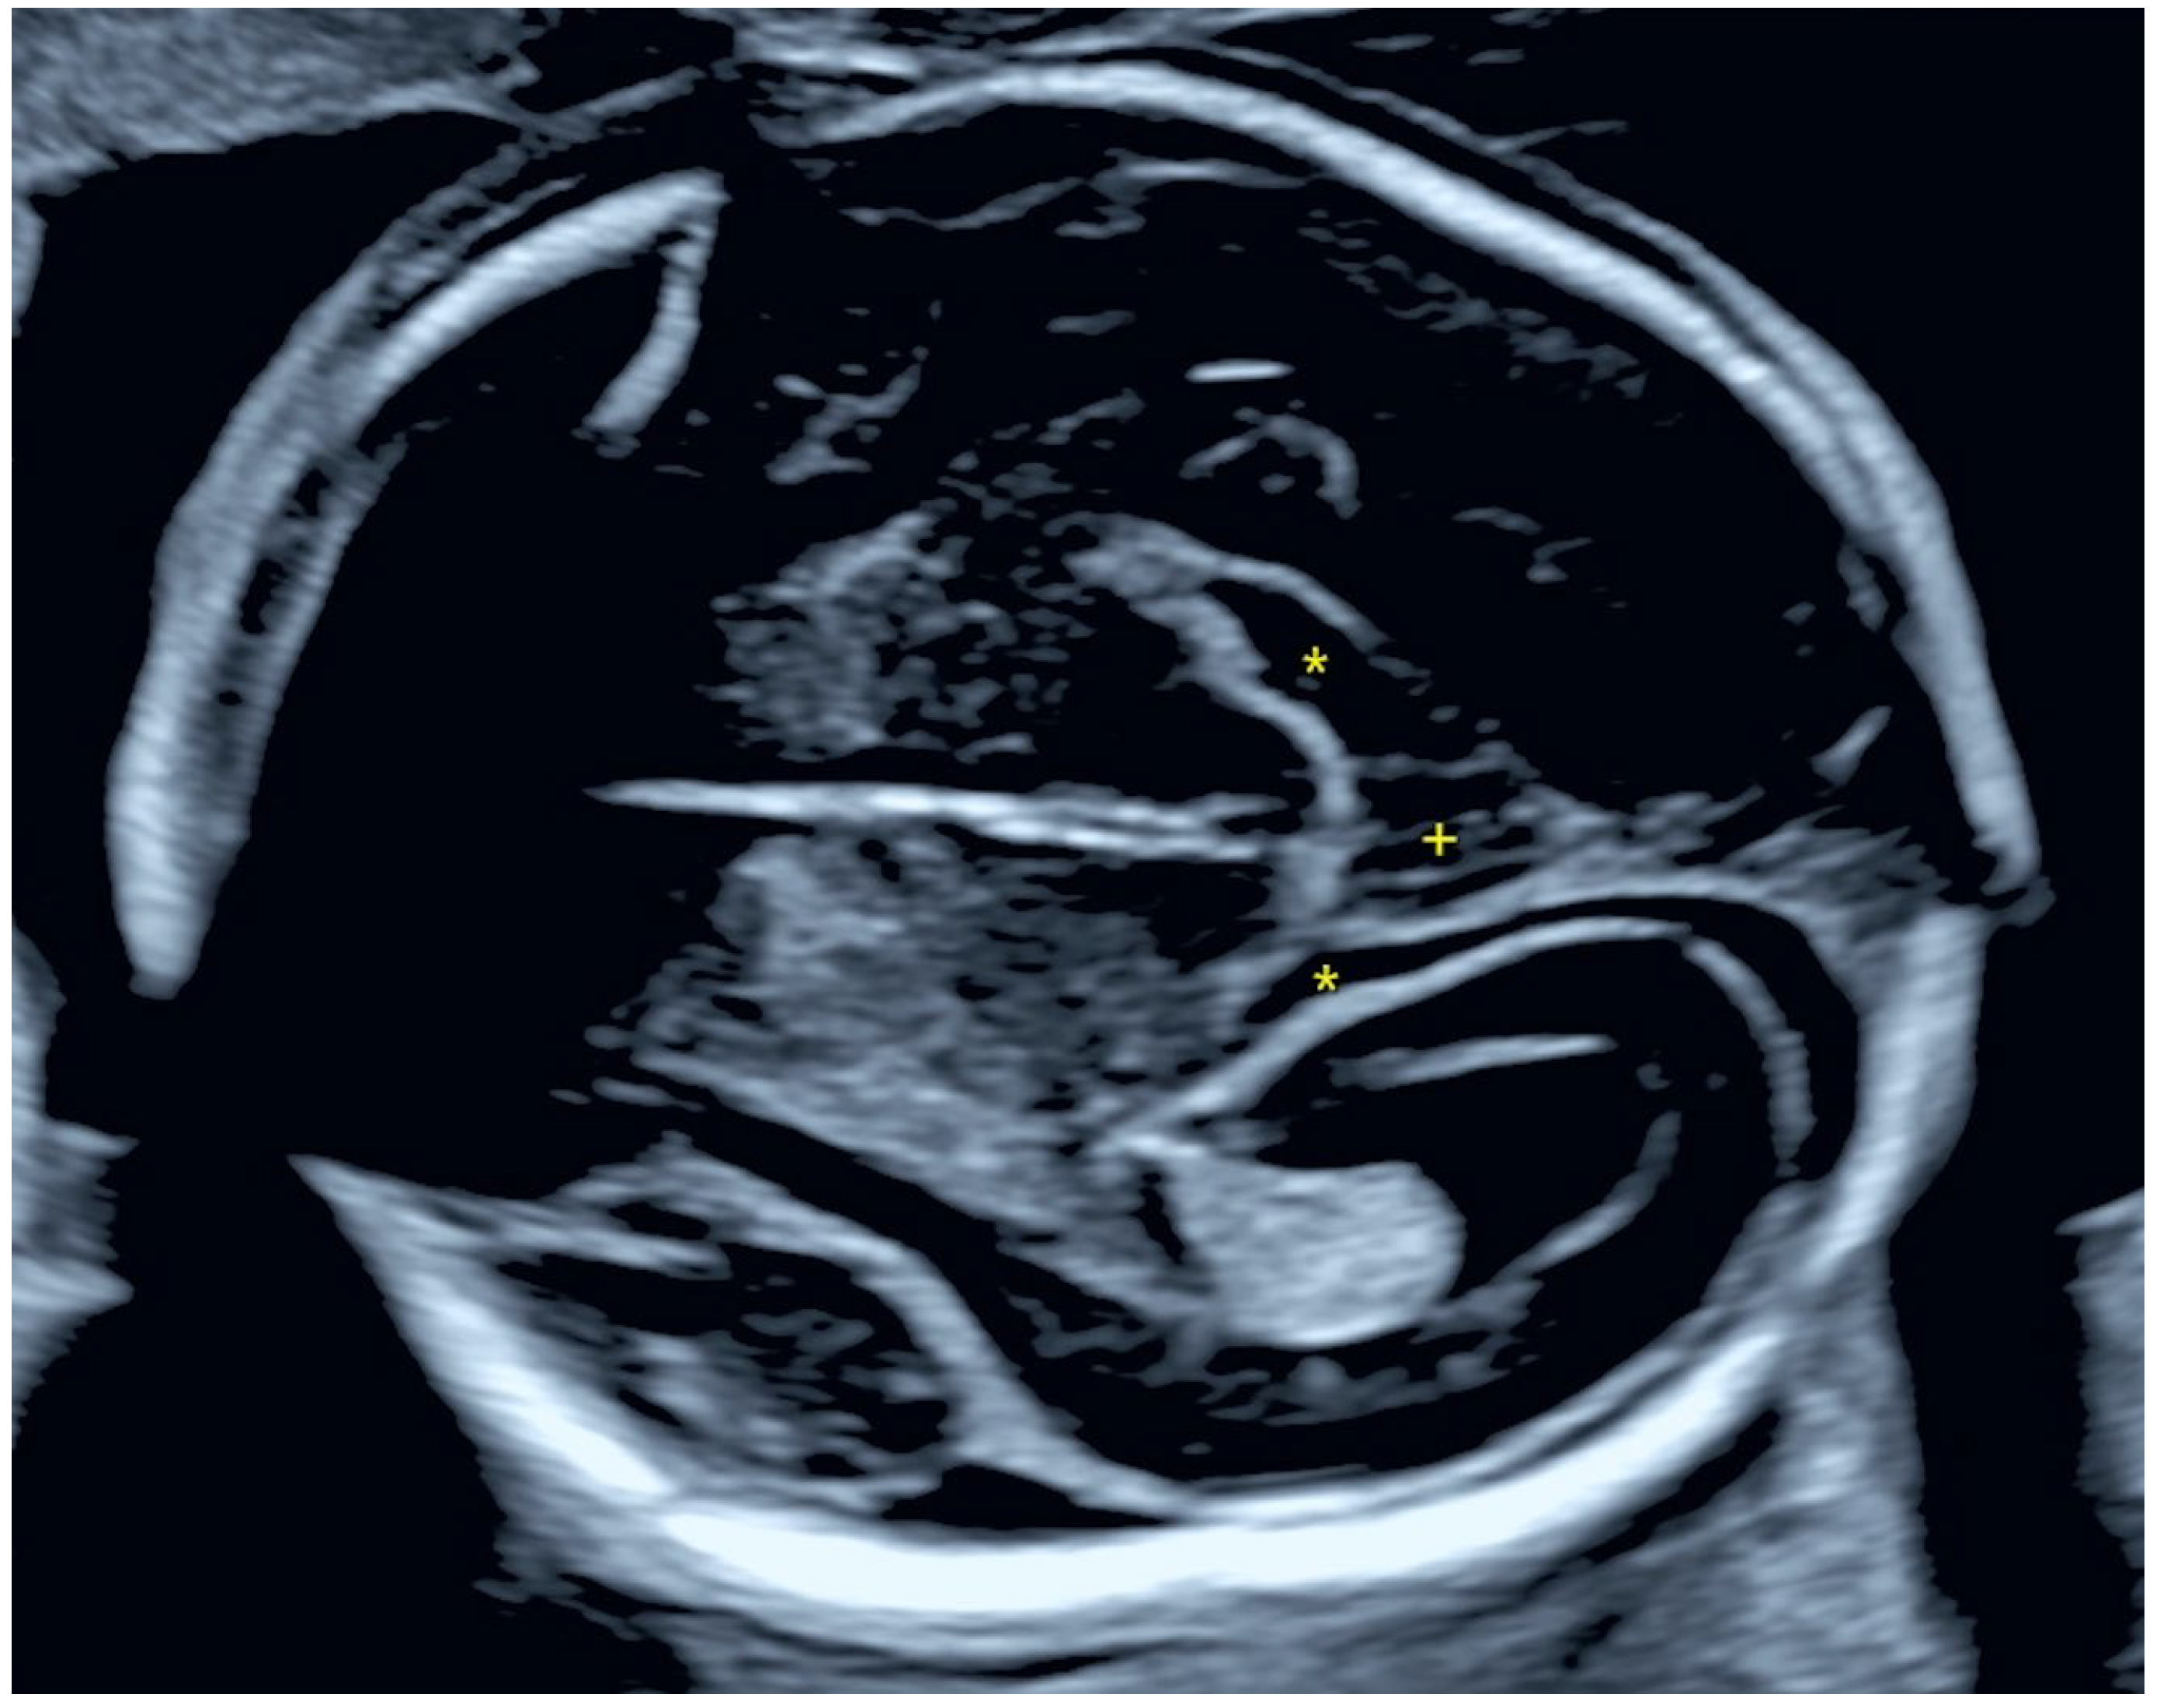

2.1.2. Ultrasound Findings

2.2.2. Ultrasound Findings